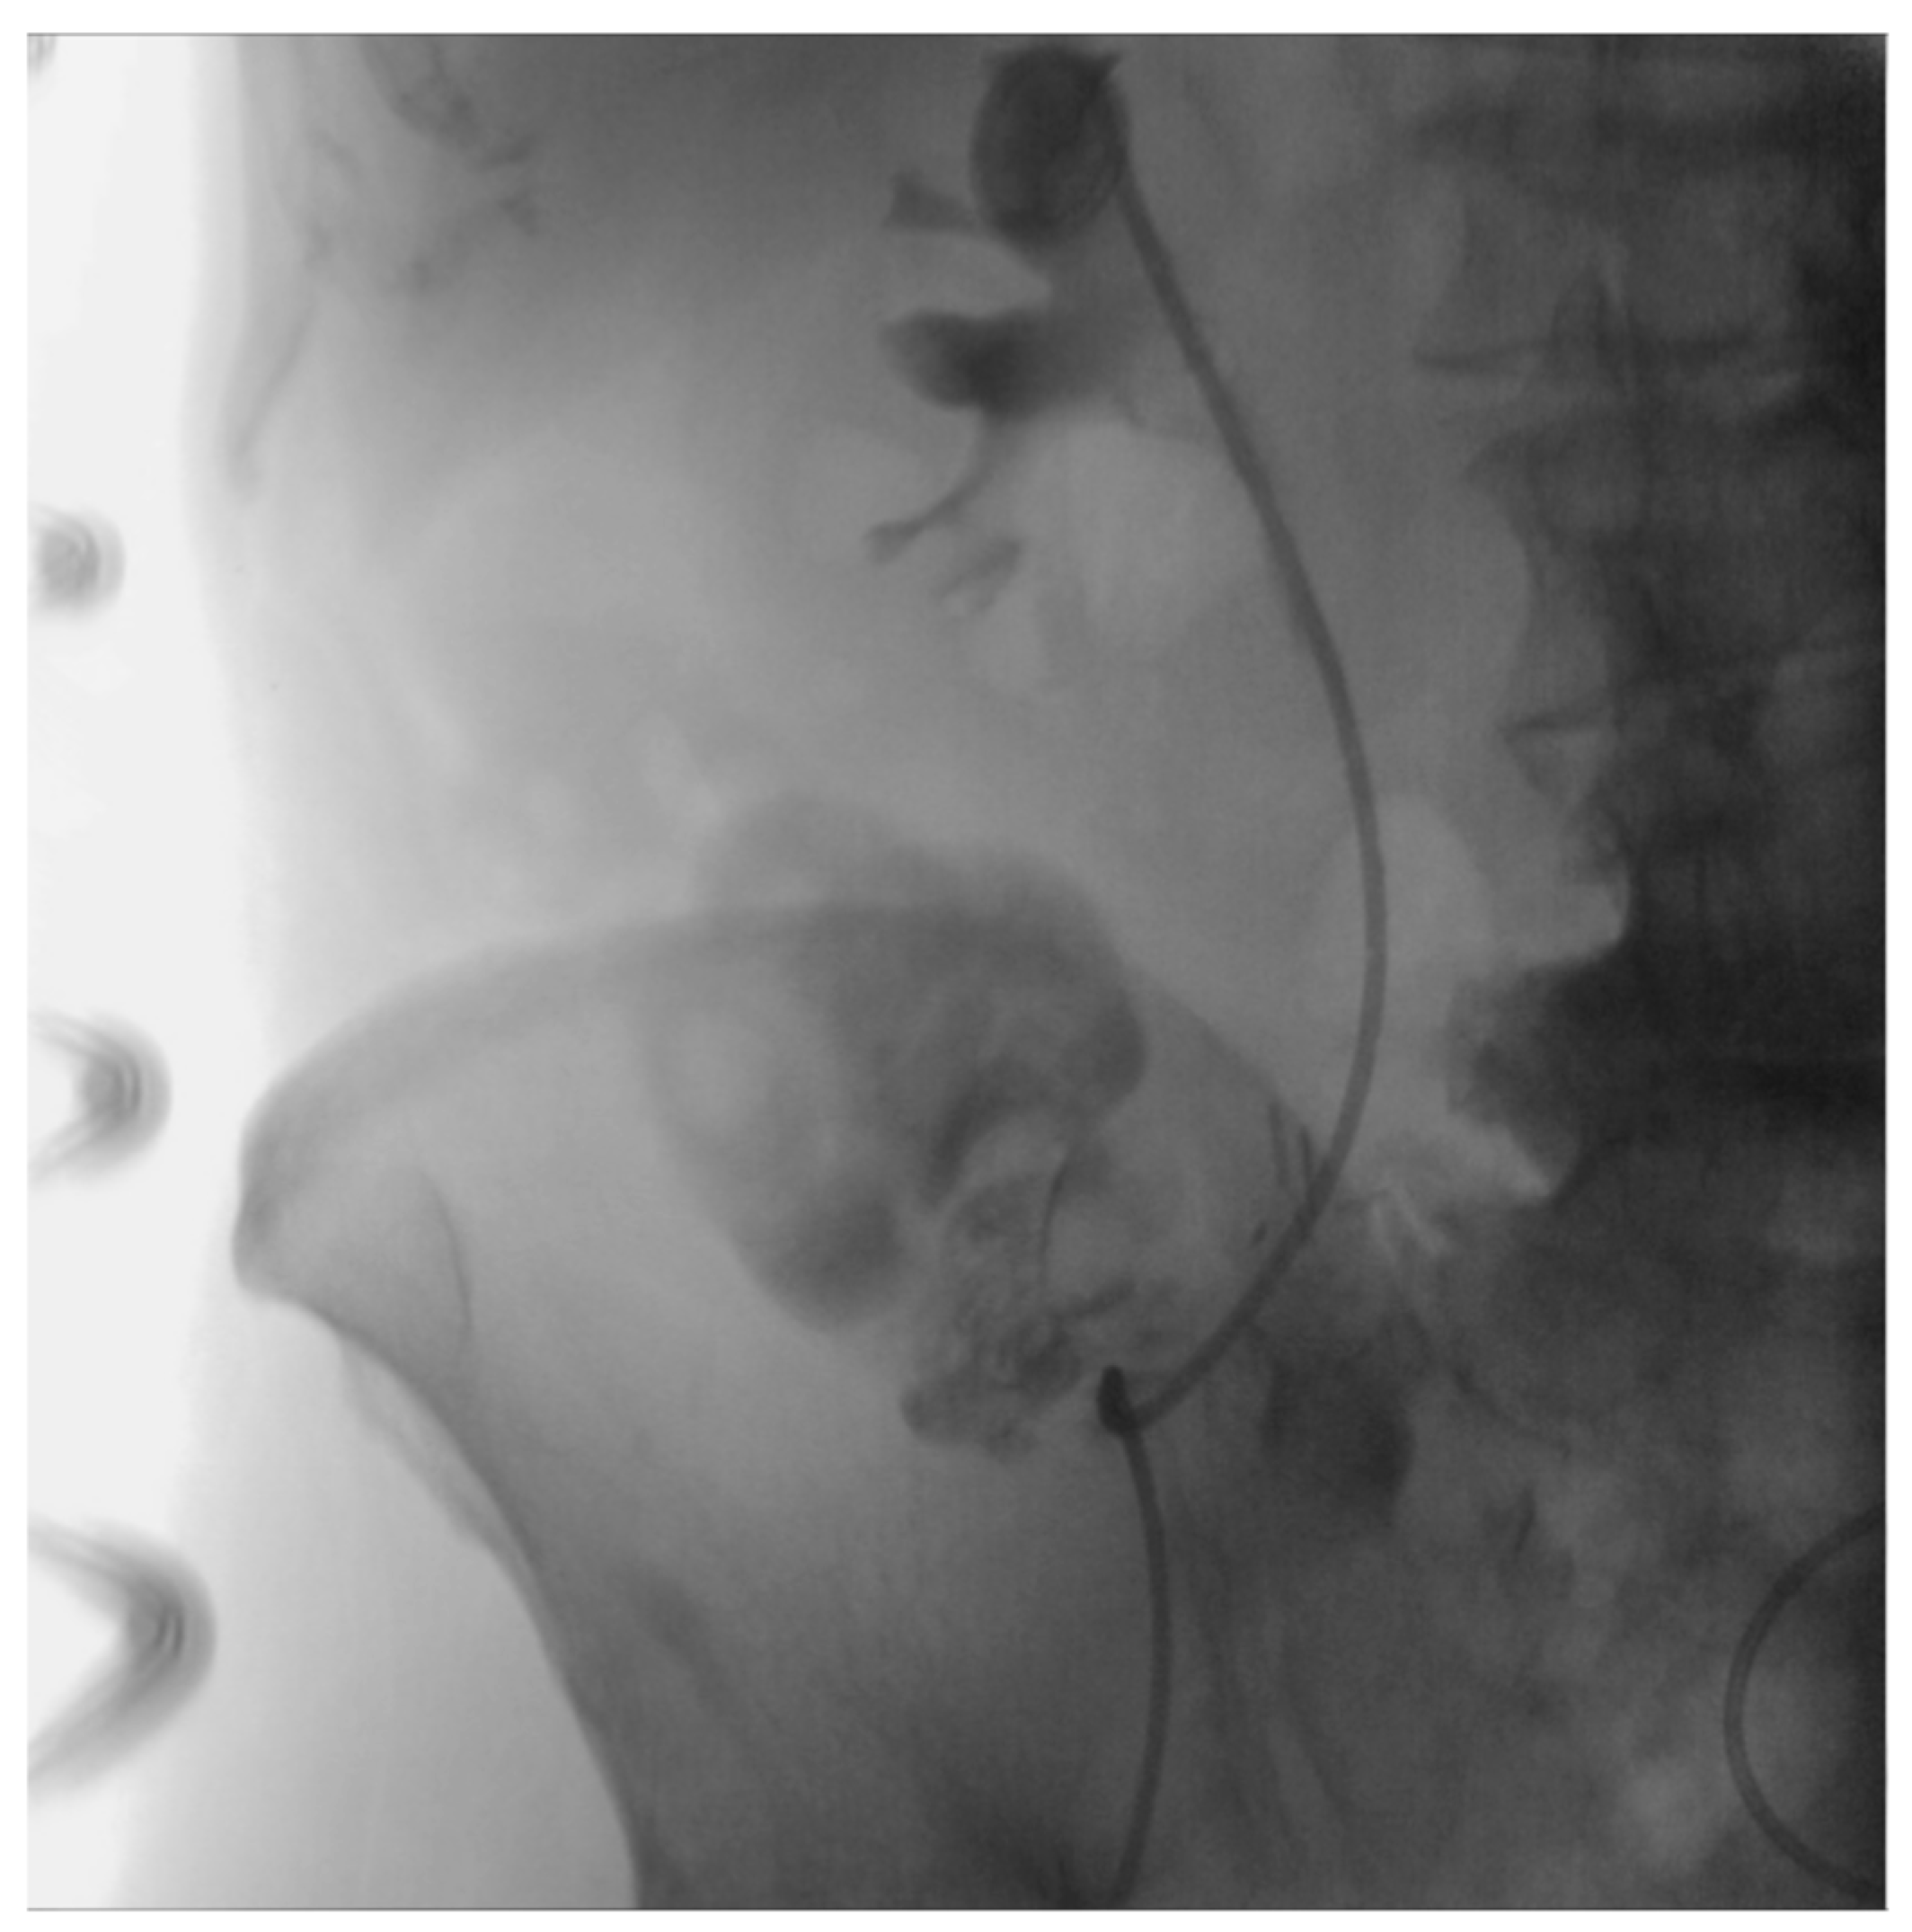

2. Case Presentation

2.2. Treatment

2.3. Outcome and Follow-Up